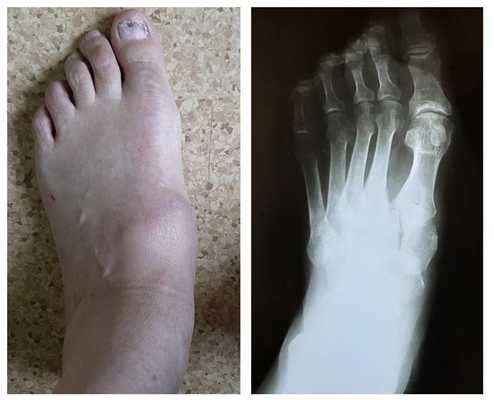

При этой деформации медиальная поверхность начинает выступать, поскольку дистальный конец плюсневой кости смещается медиально, а проксимальная фаланга отклоняется латерально. Первый плюсне-фаланговый сустав вывихивается, что приводит к латеральному отклонению большого пальца, медиальному смещению и костному разрастанию дистального конца первой плюсневой кости.

Диагностика

Рентгенография используется для определения угла между линиями, проведёнными между первой плюсневой костью и проксимальной фалангой первого пальца. Если угол больше 15°, подтверждает диагноз hallux valgus. Если угол составляет 45-50° — консервативное лечение не показано. Также должны быть определены степень смещения сесамовидных костей и уровень остеоартрита первого плюсне-фалангового сустава.

Тестирование пациента должно осуществляться два раза: в положении сидя и стоя. В положении стоя деформация стопы наиболее выражена. Во время исследования также необходимо обратить внимание на плоскостопие и степень натяжения ахиллова сухожилия, высоту продольного свода и положение большого пальца по отношению к остальным.